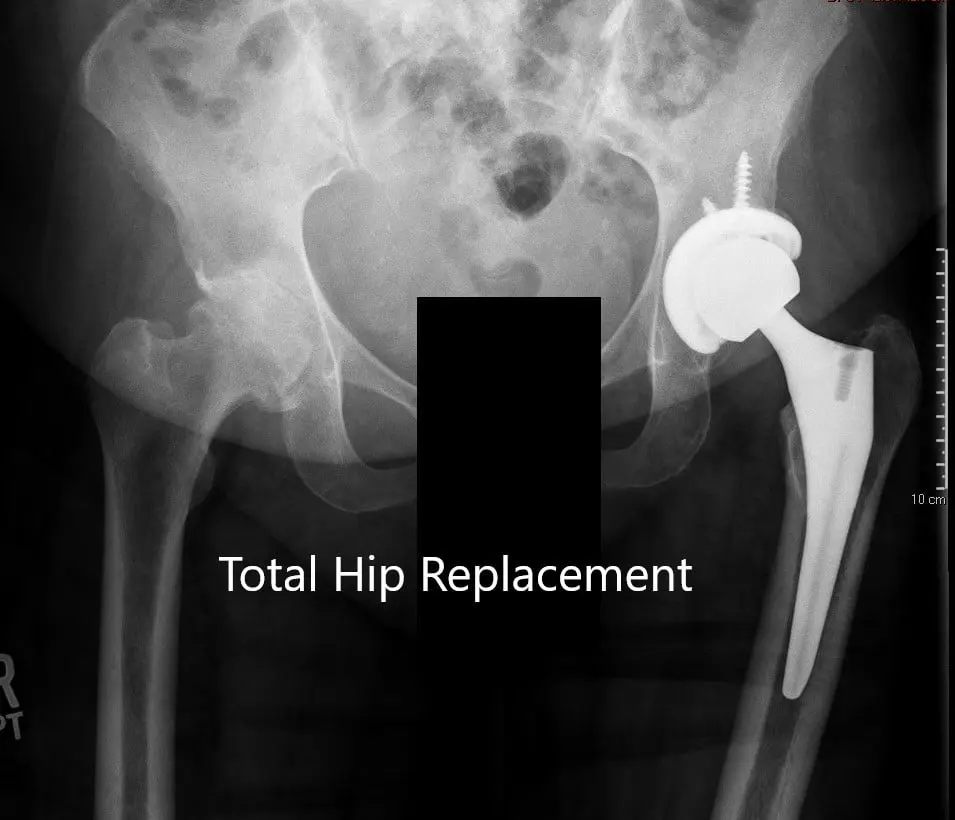

Radiografía postoperatoria que muestra la vista AP de la pelvis y la vista lateral de la cadera izquierda.